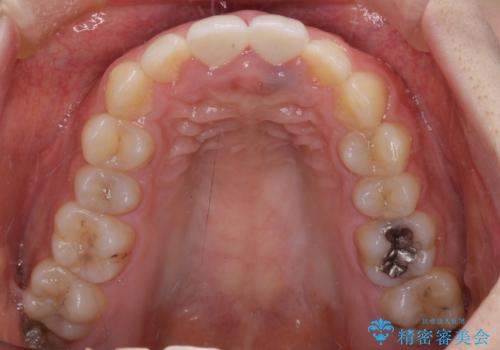

下顎前歯の部分矯正に半年ほどかかってしまい、少し期間は長いものとなりましたが、上下ともに前歯がきれいに整い、患者様には大変満足していただきました。